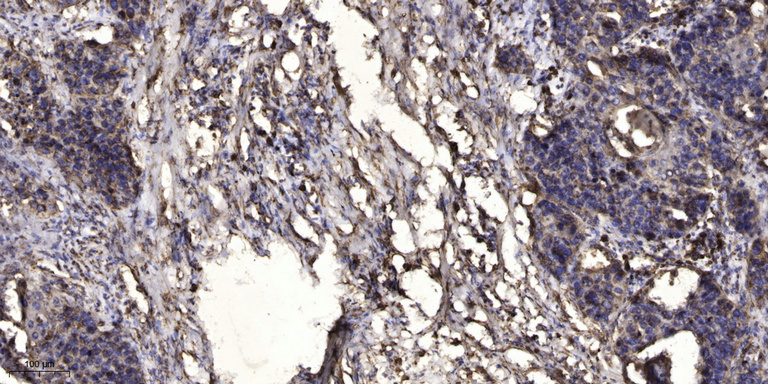

IHC (Immunohistochemistry)

(Immunohistochemical analysis of paraffin-embedded human Squamous cell carcinoma of lung. 1, Antibody was diluted at 1:200(4 degree overnight). 2, Tris-EDTA,pH9.0 was used for antigen retrieval. 3,Secondary antibody was diluted at 1:200(room temperature, 45min).)